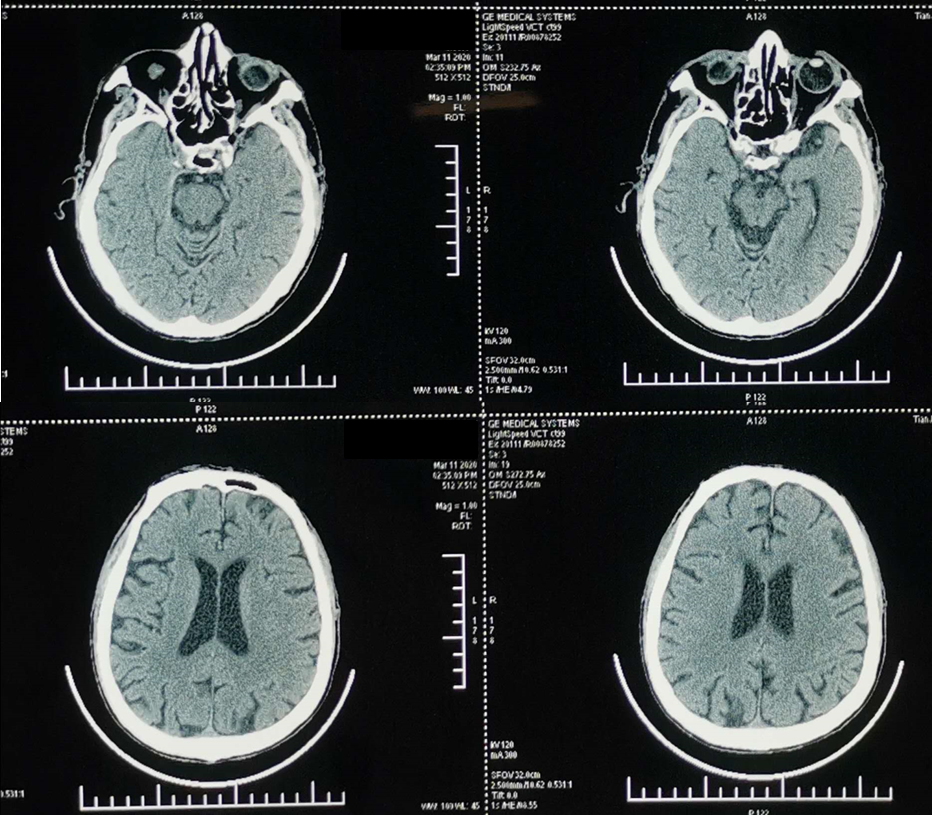

2020年1月15日至2021年2月5日,行15周期的免疫联合抗血管生成治疗。具体治疗方案为:卡瑞利珠单抗 200mg ivd qd(Q3W)+恩度 15mg×14 静脉持续泵入(Q3W)。

疗效评定:PR。

2021年4月至2022年1月,予长春瑞滨软胶囊40mg po tiw+恩度 15mg×14 静脉持续泵入(Q3W)治疗8周期,此后长春瑞滨软胶囊维持治疗至今。

疗效评定:维持PR。

治疗过程中的影像学检查结果如下图:

基于上述循证医学证据,并结合患者PD-L1高表达等病情及经济条件等因素,一线治疗给予免疫联合抗血管生成治疗。治疗过程中,复查胸部CT,可见病灶逐渐缩小。但联合治疗1年后,患者连续两次在使用ICIs后出现皮肤毒性,遂停用ICIs。此时患者病情稳定,但拒绝静脉化疗。因此,寻找一种高效、低毒且便捷的口服维持治疗方案成为临床首选。

综合考量患者的年龄、身体状况及治疗需求,临床给予长春瑞滨软胶囊节拍化疗联合恩度抗血管生成治疗。进行8个周期的联合治疗后,序贯长春瑞滨软胶囊节拍化疗长期维持。该方案取得了令人满意的成果:患者疗效持续维持PR,未出现新发转移(如颅内转移),生活质量良好。截至目前,患者已超过60个月(末次随访时间:2025年3月)未进展,为晚期ASC患者的长期生存提供了宝贵的临床经验和新的希望。